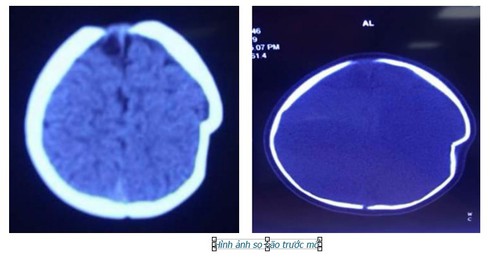

Tại đây, bé L đã được làm các xét nghiệm cận lâm sàng và được chẩn đoán lún sọ thái dương đỉnh trái.

Bác sĩ Hà Xuân Tài - Phó Khoa Ngoại Thần kinh, bác sĩ trực tiếp phẫu thuật cho bệnh nhi L cho biết: lún sọ pingpong thường gặp ở trẻ dưới 1 tuổi. Nguyên nhân thường do tai biến sinh có thủ thuật, hay trẻ bị ngã khi tập đứng, tập đi và trẻ bị ngã ở độ cao thấp. Vị trí thường gặp hộp sọ là vùng đỉnh. Do ở trẻ nhũ nhi hộp sọ có khả năng tự điều chỉnh tốt nên hiếm khi phải mổ cấp cứu ngay, trừ những trường hợp lún sọ mức độ nhiều, tổn thương rách màng cứng và tổn thương não. Tuy nhiên cha mẹ thường rất lo lắng và yêu cầu được mổ ngay vì liên quan đến thẩm mỹ hộp sọ và sợ ảnh hưởng đến thần kinh của trẻ về sau.